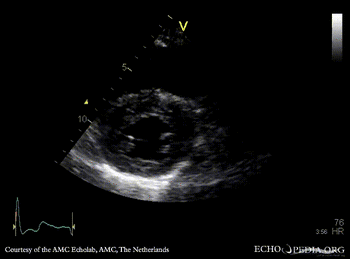

PLAX: concentric hypertrophy of left ventricle, thickend aortic valve PSAX: concentric hypertrophy of left ventricle